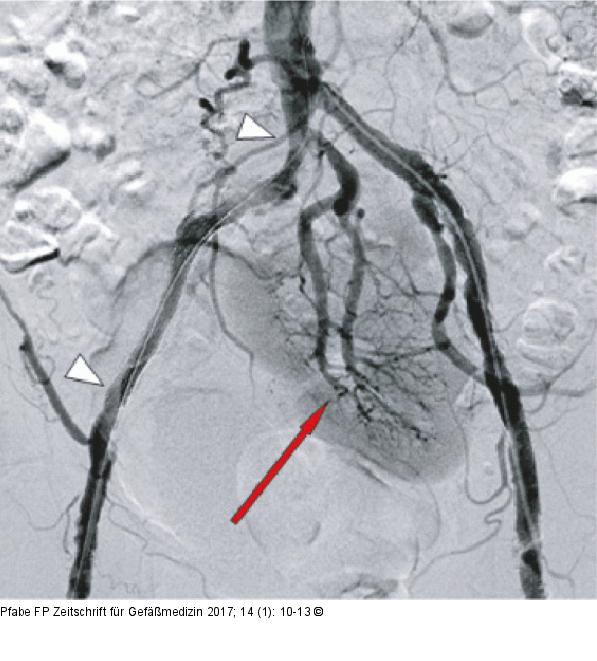

Abbildung 3: Beckenübersicht Interventionsergebnis in der DSA-Beckenübersicht nach Stentimplantation. Die weißen Pfeile markieren die Stentstrecke, erhaltene Perfusion der Kuchenniere (roter Pfeil). |

Interventionsergebnis in der DSA-Beckenübersicht nach Stentimplantation. Die weißen Pfeile markieren die Stentstrecke, erhaltene Perfusion der Kuchenniere (roter Pfeil). |